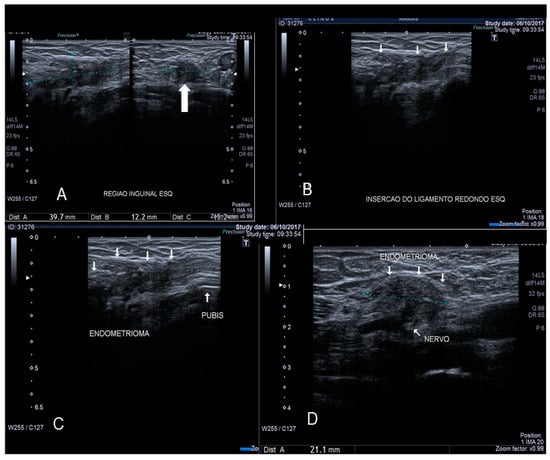

The canal of Nuck is a small protrusion of the parietal peritoneum which is attached to the uterus by the round ligament through the internal inguinal ring into the inguinal canal. Cullen first reported endometriosis of the inguinal canal in 1896. This site of endometriosis is quite rare, with a reported incidence of about 0.6% [21]. The inguinal canal may become a site of ectopic implants of endometrial tissue by direct extension of the endometrial cells from the uterine cavity to the inguinal canal through the round ligament which may, on occasion, remain patent, thus creating a communication between the peritoneal cavity and the inguinal canal [22] (Figure 9 and Figure 10). Inguinal endometriosis usually occurs on the right side (90% of cases), often alongside an inguinal hernia. It may be suspected in the presence of an inguinal mass that may swell and cause painful symptoms, particularly during menses [21].

Inguinal endometriosis is quite variable in its ultrasonographic presentation. It may appear as a completely solid mass (Figure 9) or a mixed solid and cystic mass (Figure 10). Cystic masses can be hypo or hyperechoic [22] and usually there is evidence of peripheral vascularization at Doppler evaluation (Figure 9).

Figure 10. Sonographic features of solid inguinal endometriosis (see thin and thick with arrows) (AD).